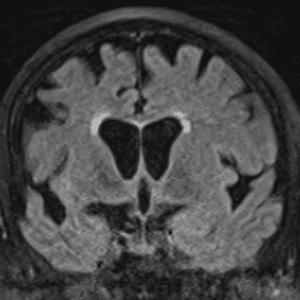

Neurodegenerative Diseases